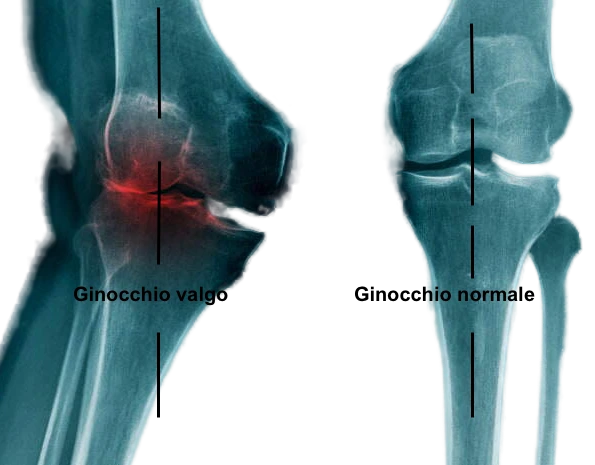

Varismo (gambe a “O”): accentua il sovraccarico del compartimento mediale, aumentando il rischio di artrosi interna.

Valgismo (gambe a “X”): accentua il sovraccarico del compartimento esterno, favorendo l’usura della cartilagine laterale.

In condizioni normali l’asse meccanico di carico dell’arto inferiore passa per il centro del ginocchio, le forze di carico sono quindi distribuite uniformemente su tutta l’articolazione. Nel caso del ginocchio varo, il comparto interno del ginocchio viene ad essere sovraccaricato, causandone la progressiva usura. Nel ginocchio valgo, è il comparto esterno ad essere maggiormente sollecitato dalle forze di carico

Il ginocchio varo o valgo provoca una distribuzione asimmetrica del carico sull’articolazione, causando una maggiore usura di una sola porzione della cartilagine. Questo può tradursi in dolore, rigidità e limitazione dei movimenti.

Attraverso l’osteotomia, il chirurgo corregge l’allineamento dell’arto inferiore, spostando l’asse di carico dal comparto danneggiato al centro dell’articolazione. In questo modo si ottiene una riduzione significativa del dolore e un miglioramento della funzionalità del ginocchio.